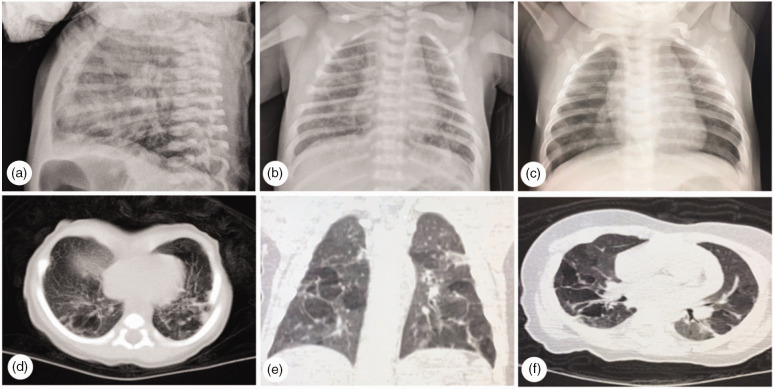

单绒毛膜单羊膜双胞胎妊娠是非常罕见的,经常导致并发症。然而,在单绒毛膜单羊膜双胎妊娠中,没有单胎宫内死亡后存活胎儿肺损伤的报道。据我们所知,我们首次报道了单绒毛膜单羊膜双胎妊娠中单个宫内胎儿死亡后存活胎儿的肺和脑损伤。一名男婴出生时呼吸困难。他健康的39岁母亲是单绒毛膜单羊膜双胎妊娠。一个胎儿在妊娠17+2周心脏骤停后,存活的胎儿从19周开始出现轻微的双侧心室扩张。通过剖宫产与死亡胎儿一起分娩,存活的胎儿表现出肺和脑损伤,并在10天大时出院。在排除其他新生儿疾病后,他的长期炎性肺损伤被认为与单一宫内胎儿死亡有关。本病例提醒妇产科医生,单胎宫内死亡可引起单绒毛膜单羊膜双胎存活胎儿肺吸入和脑缺血-缺氧损伤。产前评估和产后随访对这类高危妊娠至关重要。

Pregnancy with monochorionic monoamniotic twins is highly rare and frequently results in complications. Nevertheless, in monochorionic monoamniotic twin pregnancies, there are no reports of lung injury in the surviving fetus after single intrauterine fetal death. To the best of our knowledge, we present the first report of lung and brain injuries in a surviving fetus after single intrauterine fetal death in a monochorionic monoamniotic twin pregnancy. A male child was born with dyspnea. His healthy 39-year-old mother had a monochorionic monoamniotic twin pregnancy. After the cardiac arrest of one fetus at 17+2 weeks of gestation, the surviving fetus showed slight bilateral ventricular dilatation from 19 weeks. Delivered full-term alongside the deceased fetus via cesarean section, the surviving fetus exhibited lung and brain injuries and was discharged at 10 days old. His prolonged inflammatory lung injury was considered related to single intrauterine fetal death, after ruling out other neonatal conditions. This case reminds obstetricians and pediatricians that single intrauterine fetal death could cause pulmonary inhalation and cerebral ischemic-hypoxic injury in monochorionic monoamniotic twin surviving fetuses. Antenatal evaluation and postnatal follow-up are essential in this type of high-risk pregnancy.